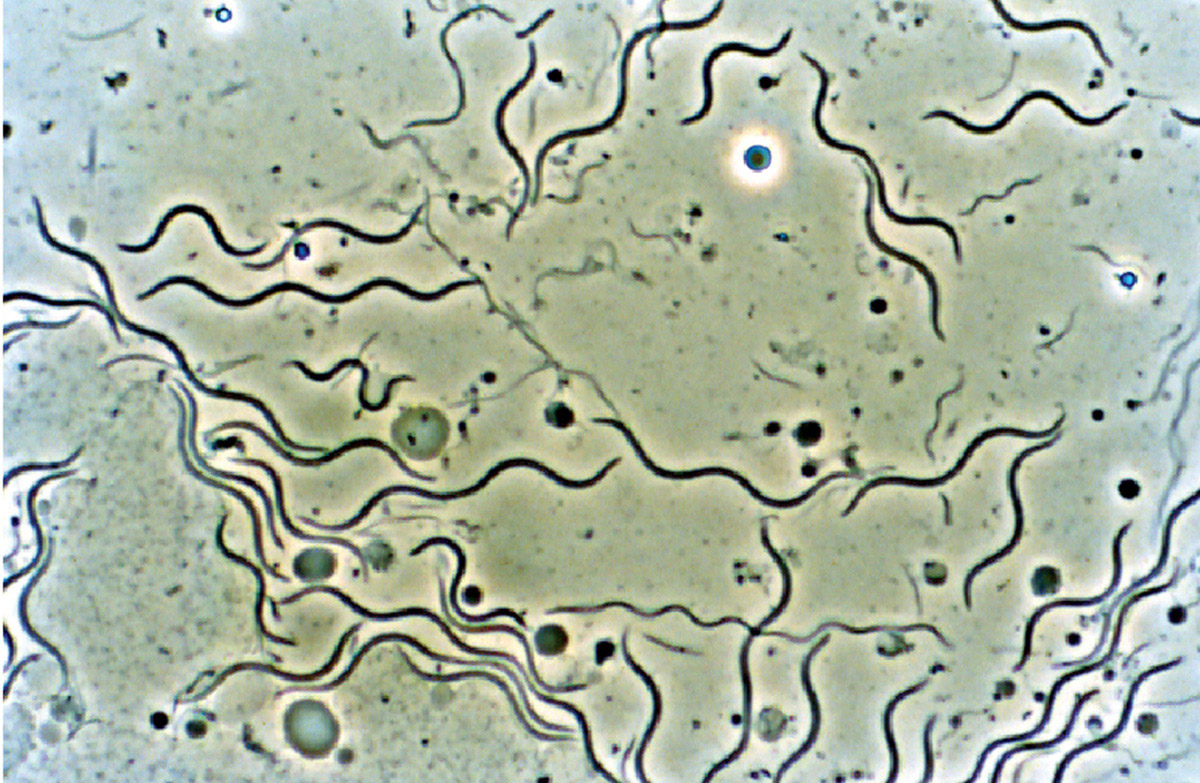

Лептоспиры: фотографии удивительных микроорганизмов

:max_bytes(150000):strip_icc():format(webp)/spirillum-56a09b3b3df78cafdaa32ecc.jpg)